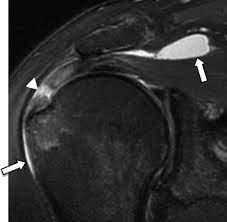

MRI (Magnetic Resonance Imaging)

MRI is a non-invasive imaging technique that uses a powerful magnet and radio waves to create detailed images of the internal structures of the body. In the context of subacromial bursitis, an MRI can provide high-resolution images of the soft tissues, including the subacromial bursa, tendons, muscles, and bones in the shoulder.

Advantages of MRI in Subacromial Bursitis

- Detailed Visualization : MRI provides detailed and multi-planar images, allowing for a comprehensive assessment of the subacromial space and surrounding structures.

- Soft Tissue Contrast : MRI excels in differentiating between various soft tissues, helping to identify inflammation, fluid accumulation, and structural abnormalities in the subacromial bursa.

- Detection of Other Pathologies : MRI can also reveal other shoulder pathologies, such as rotator cuff tears or ligament injuries, which may coexist with subacromial bursitis.

Clinical Use

- Confirmation of Diagnosis : Both MRI and ultrasound can help confirm the diagnosis of subacromial bursitis by visualizing signs of inflammation, such as fluid accumulation within the bursa.

- Differential Diagnosis : These imaging studies aid in ruling out other shoulder pathologies that may present with similar symptoms.

- Treatment Planning : Imaging findings guide healthcare professionals in developing an appropriate treatment plan, whether it involves conservative measures, physical therapy, or interventional procedures like bursa injections.